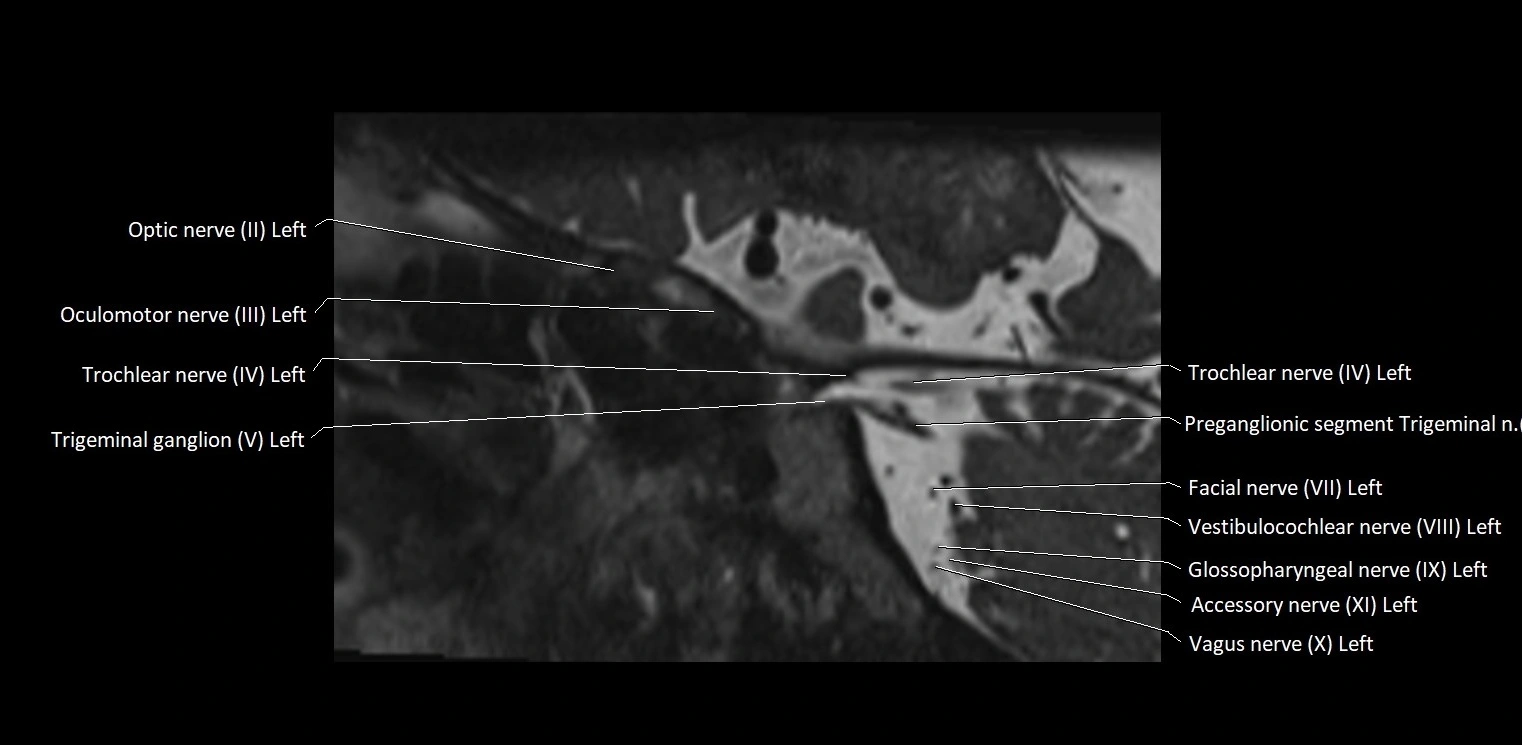

MRI Appearance

• The abducens nerve is a small, thin, linear structure

• Best visualized on high-resolution T2-weighted 3D MRI sequences (e.g., FIESTA or CISS)

• Seen as a hypointense (dark) line running from the brainstem at the pontomedullary junction, traversing the prepontine cistern, and entering Dorello’s canal under the petrosphenoidal ligament, then into the cavernous sinus, and finally the orbit

• May be challenging to visualize in standard MRI due to its small size

• Pathology may be inferred by absence, displacement, or enhancement of the nerve